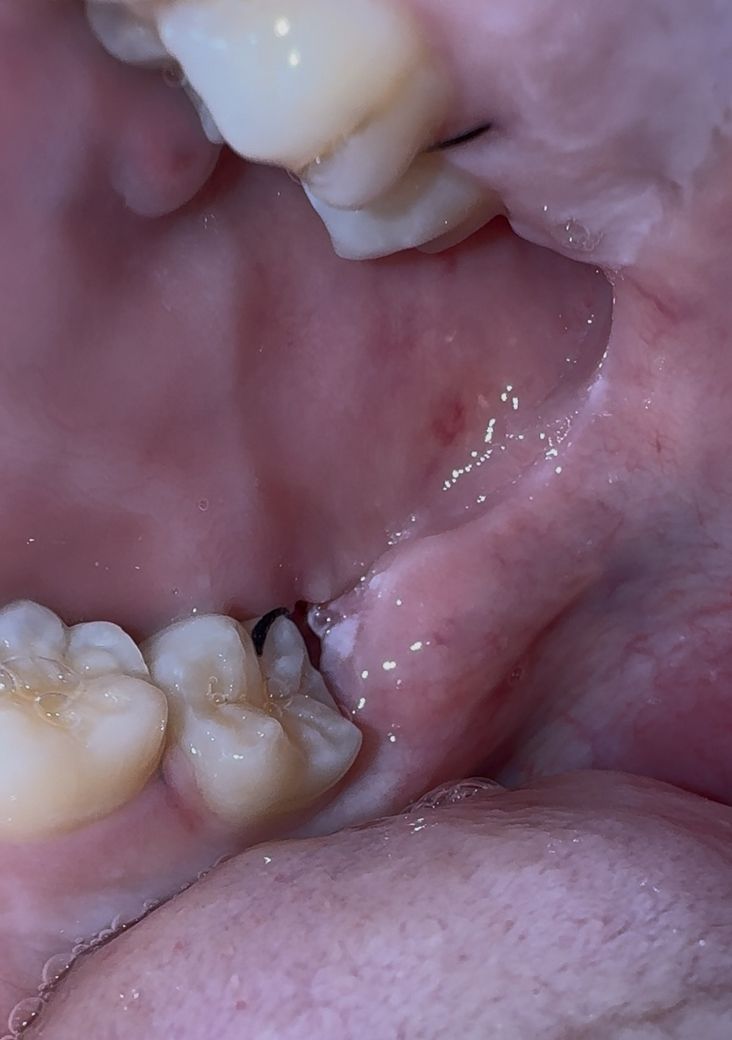

사랑니 발치 3일차인데 실밥 풀린건가요?

아래 수평매복사랑니하고 위에 그냥 사랑니 수요일 오후에 발치하고 3일차인데 입 안을 보니 실밥이 저렇게 되어있네요. 실밥이 풀린건가요?

실밥이 풀린건 아니고 붓기가 빠지면서 실밥이 느슨해진거 같습니다. 큰문제가 잇는건 아니니 걱정하지 않으셔도 될것같습니다.

실밥이 남아있어보이지만 풀렸는지 여부는 직접 봐야할듯하며 풀렸다면 손으로 쉽게 나올겁니다.

사랑니를 발치하고 나면 실밥이 풀리거나 할수 있습니다. 크게 문제가 되지는 않기 때문에 너무 걱정하지 않으셔도 될것으로 생각됩니다.